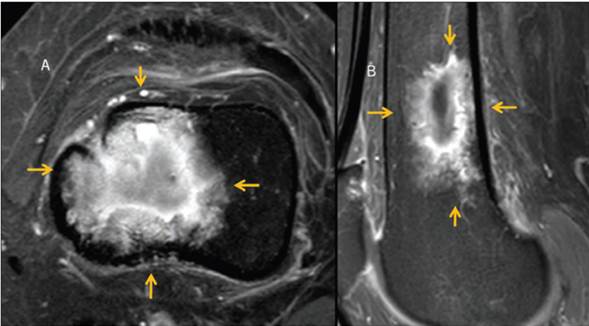

En septiembre se obtuvieron nuevas placas de rodilla, ahora con mínimas lesiones, y se decidió tomar nueva RM (Figura 8) que mostró tumor del espacio que afecta la porción central de la médula ósea, del tercio distal de contornos irregulares, espiculados con intensidad de señal heterogénea en todas las secuencias y mostró realce periférico con la aplicación de gadolinio, hipointenso en T1 e hiperintensa en T2, con afectación de la cortical por la toma de la biopsia. En octubre se ajustó el tratamiento con talidomida durante 7 días 2 veces al mes y continúa igual con dexametasona; Se indicó radioterapia a rodilla izquierda para tratar enfermedad residual.